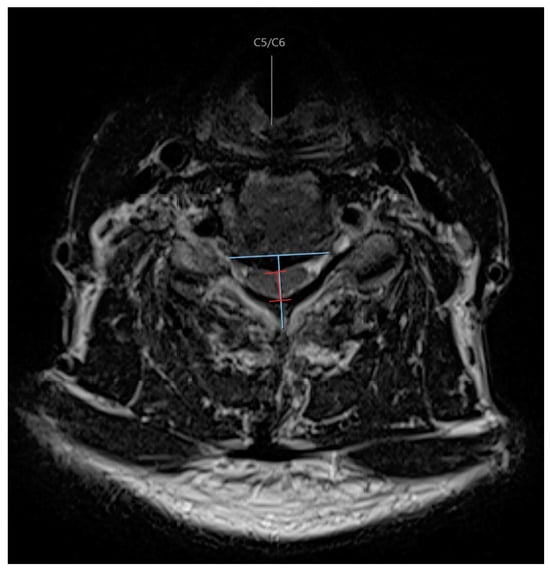

The radiographic compression side was determined by a line estimated to be perpendicular to the midline of the posterior aspect of the vertebral body/disc of the level in question, and if the apex of maximal compression was located to the right or left of that line (Figure 1). This was measured at each level on axial T2-weighted MRI images by two independent reviewers with a specialty in spine surgery. If there was a discrepancy about the side of compression at any level for any patient, then a third reviewer was used. The third reviewer used the same criteria, and the majority of the three reviewers was used to designate the compression side. To assign each patient with an overall classification of the side of compression, if most levels were compressed on one side, this was considered the dominant side of compression. If there was an equal number of levels compressed on the right and left sides, then the most stenotic level dictated the overall compression side. This allowed us to create a group of patients that had the opening side of laminoplasty on either the ipsilateral or contralateral side to dominant radiographic compression.

Space available for the spinal cord (SAC) was measured at each level, where maximal compression was noted on T2-weighted axial images. The SAC was measured as the diameter of the spinal canal on midline axial images considered the maximal distance from the source of compression to the posterior elements. The SAC was taken as the average between two independent reviewers.

Figure 1. Axial T2-weighted MRI demonstrating radiographic measurements to determine the side of compression and canal diameter.